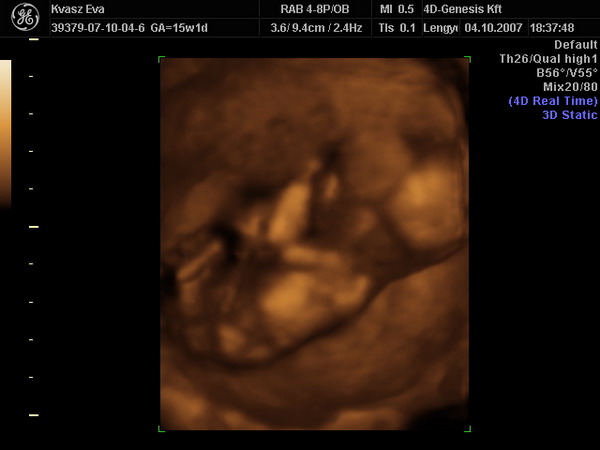

Bence 18 hetesen